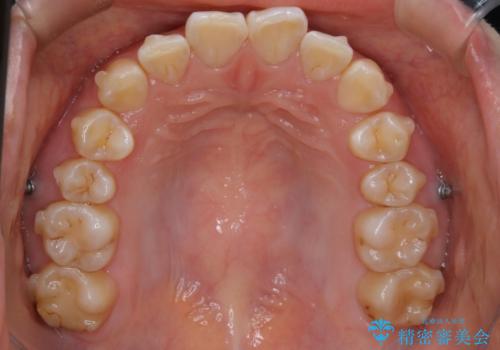

【非抜歯】ガタつきと歯軸を正して長持ちする歯へ

- 歯のガタつきと噛み合わせの改善を主訴に来院されました。

非抜歯で、少量の奥歯の移動と歯列の拡大・IPRを駆使して主訴を改善するための治療計画を立案しました。